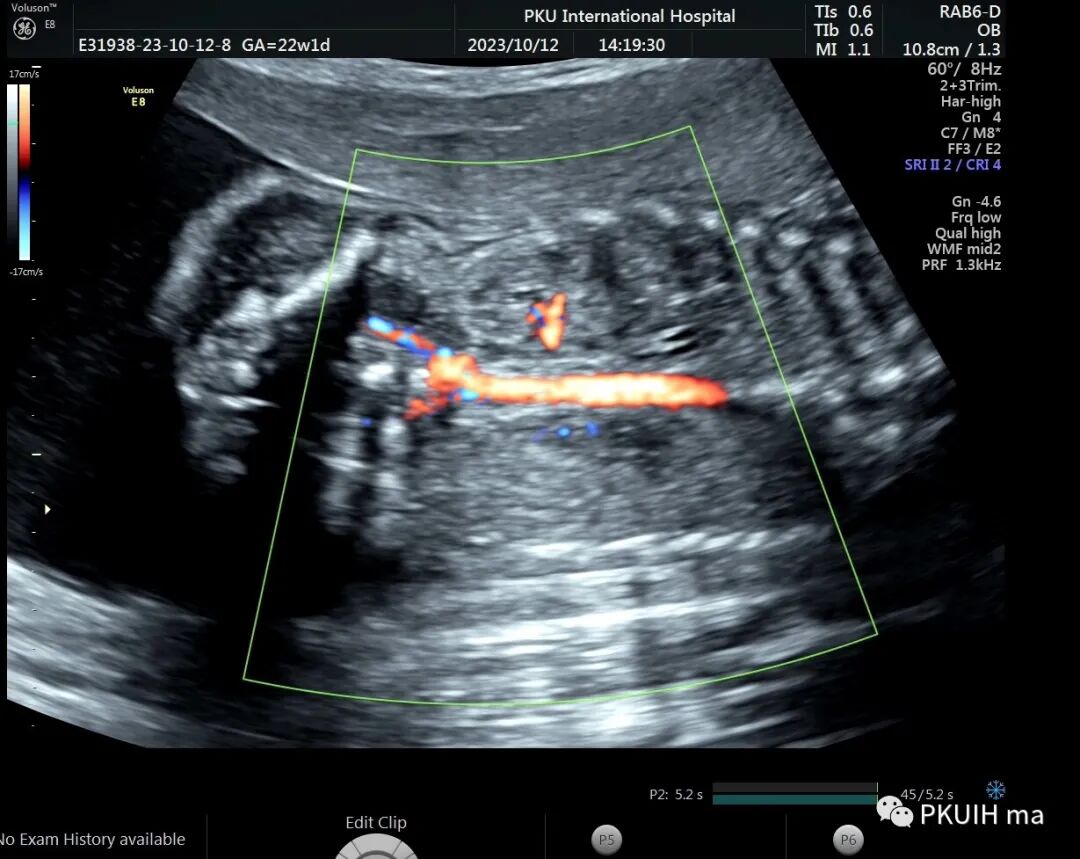

右肾大小位置正常,右肾动脉可见,左肾动脉缺如,正常的左肾区未见肾组织回声,可见肾上腺平卧。于膀胱后上方见一肾组织回声,大小约1.5x1.4x1.0cm,皮髓质分界欠清晰,血供来源于髂动脉。

异位肾较常见,发生率约1/1200,目前产前确诊并不困难。异位肾最常见的就是盆腔异位肾,占异位肾的一半以上,往往合并发育不良。血供可来源于腹主动脉或髂动脉,部分可有血管迷走。超声诊断标准:1、一侧肾区内未见肾组织回声;2、同侧的肾上腺呈平卧征;3、对侧肾可增大也可正常;4、盆腔可见一发育不良或发育正常的肾脏回声;5、可合并其他畸形,比如输卵管发育畸形或者是Vacterl综合征。